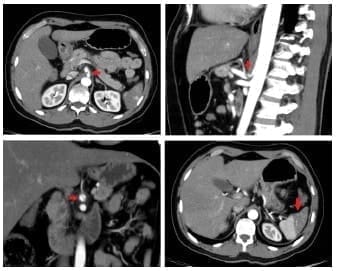

De manera consensuada con radiología se solicitó una angiotomografía para esclarecer la lesión vascular, encontrando una disección contenida del tronco celíaco y autolimitada a la arteria hepática común, después del origen de la arteria gástrica izquierda y antes del origen de la arteria gastroduodenal, sin presencia de aneurismas. No se encontró compromiso isquémico de las vísceras (figura 2).

Figura 2. Disección contenida del tronco celíaco autolimitada en la arteria hepática común después del origen de la arteria gástrica izquierda y antes del origen de la arteria gastroduodenal (flecha roja). No se observan aneurismas o placas ateromatosas, se observan áreas de infarto esplénico.